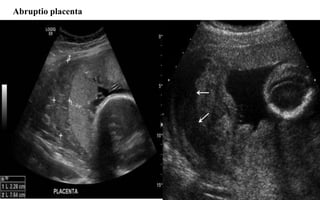

Abruptio placenta